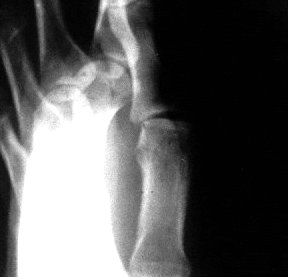

Thumb MCP RCL stress Xray view

Xray beam angle 90 degrees.